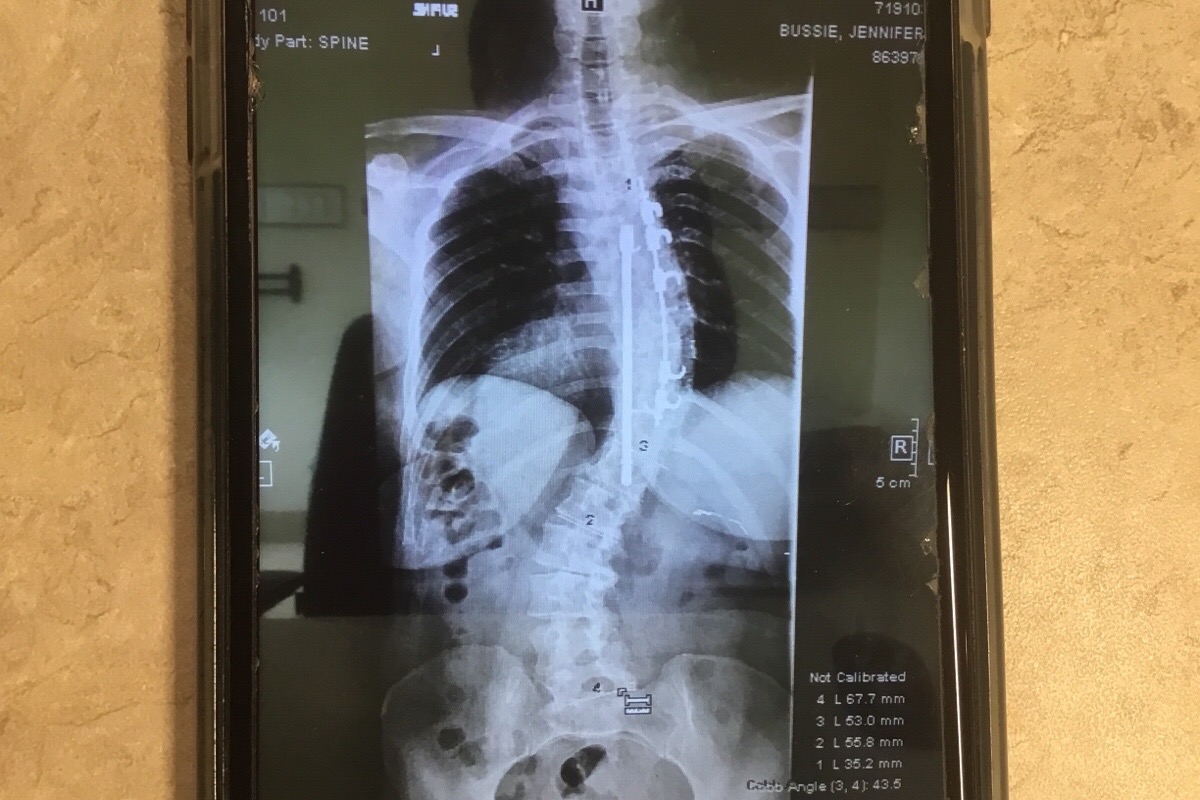

This photo is a current x-ray of the back of one of the most Godly, amazing, and loving women I know. She had her first scoliosis surgery 34 years ago, where they installed the hardware you can see in this photo. Over the last several years my friend has suffered from severe pain, numbness in her arm and hand and also loosing the feeling in her left foot. After much prayer and petition Jennifer and her husband Ted sought out the help of a doctor in NYC. This doctor hand picks his patients. After her first consult with this doctor, he picked Jen. Tomorrow 8/19/19, Jennifer will have all her old hardware removed and receive new hardware. She will be in ICU for a day or two then in a regular room for five days. After being discharged she has to stay at a nearby hotel for a week. With several follow up visits in the near future. This is where you come in. Ted and Jennifer are small business owners and when small business owners can’t work there’s no money coming. Theses trips from Alabama to NYC are very expensive with air fare, hotels, food, and transit systems in the city. They have thirteen children with five of them still small and living at home. Please be in prayer for all of them. If you can find it in your heart to donate too, I along with my amazing friends, will be forever grateful.